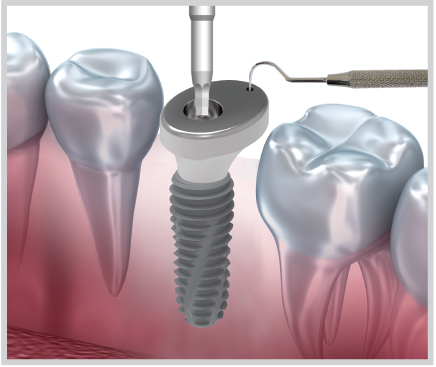

Screw가 내장된 Volume Up Healing Abutment를 Fixture에 체결

-

체결 시 Explorer Tip을 이용하여

Abutment 방향 변동 방지 -

Easy Seal 등과 같은 수복재로

Screw Hole 충전

* 주의사항: 식립 torque 값 25N.cm 이상